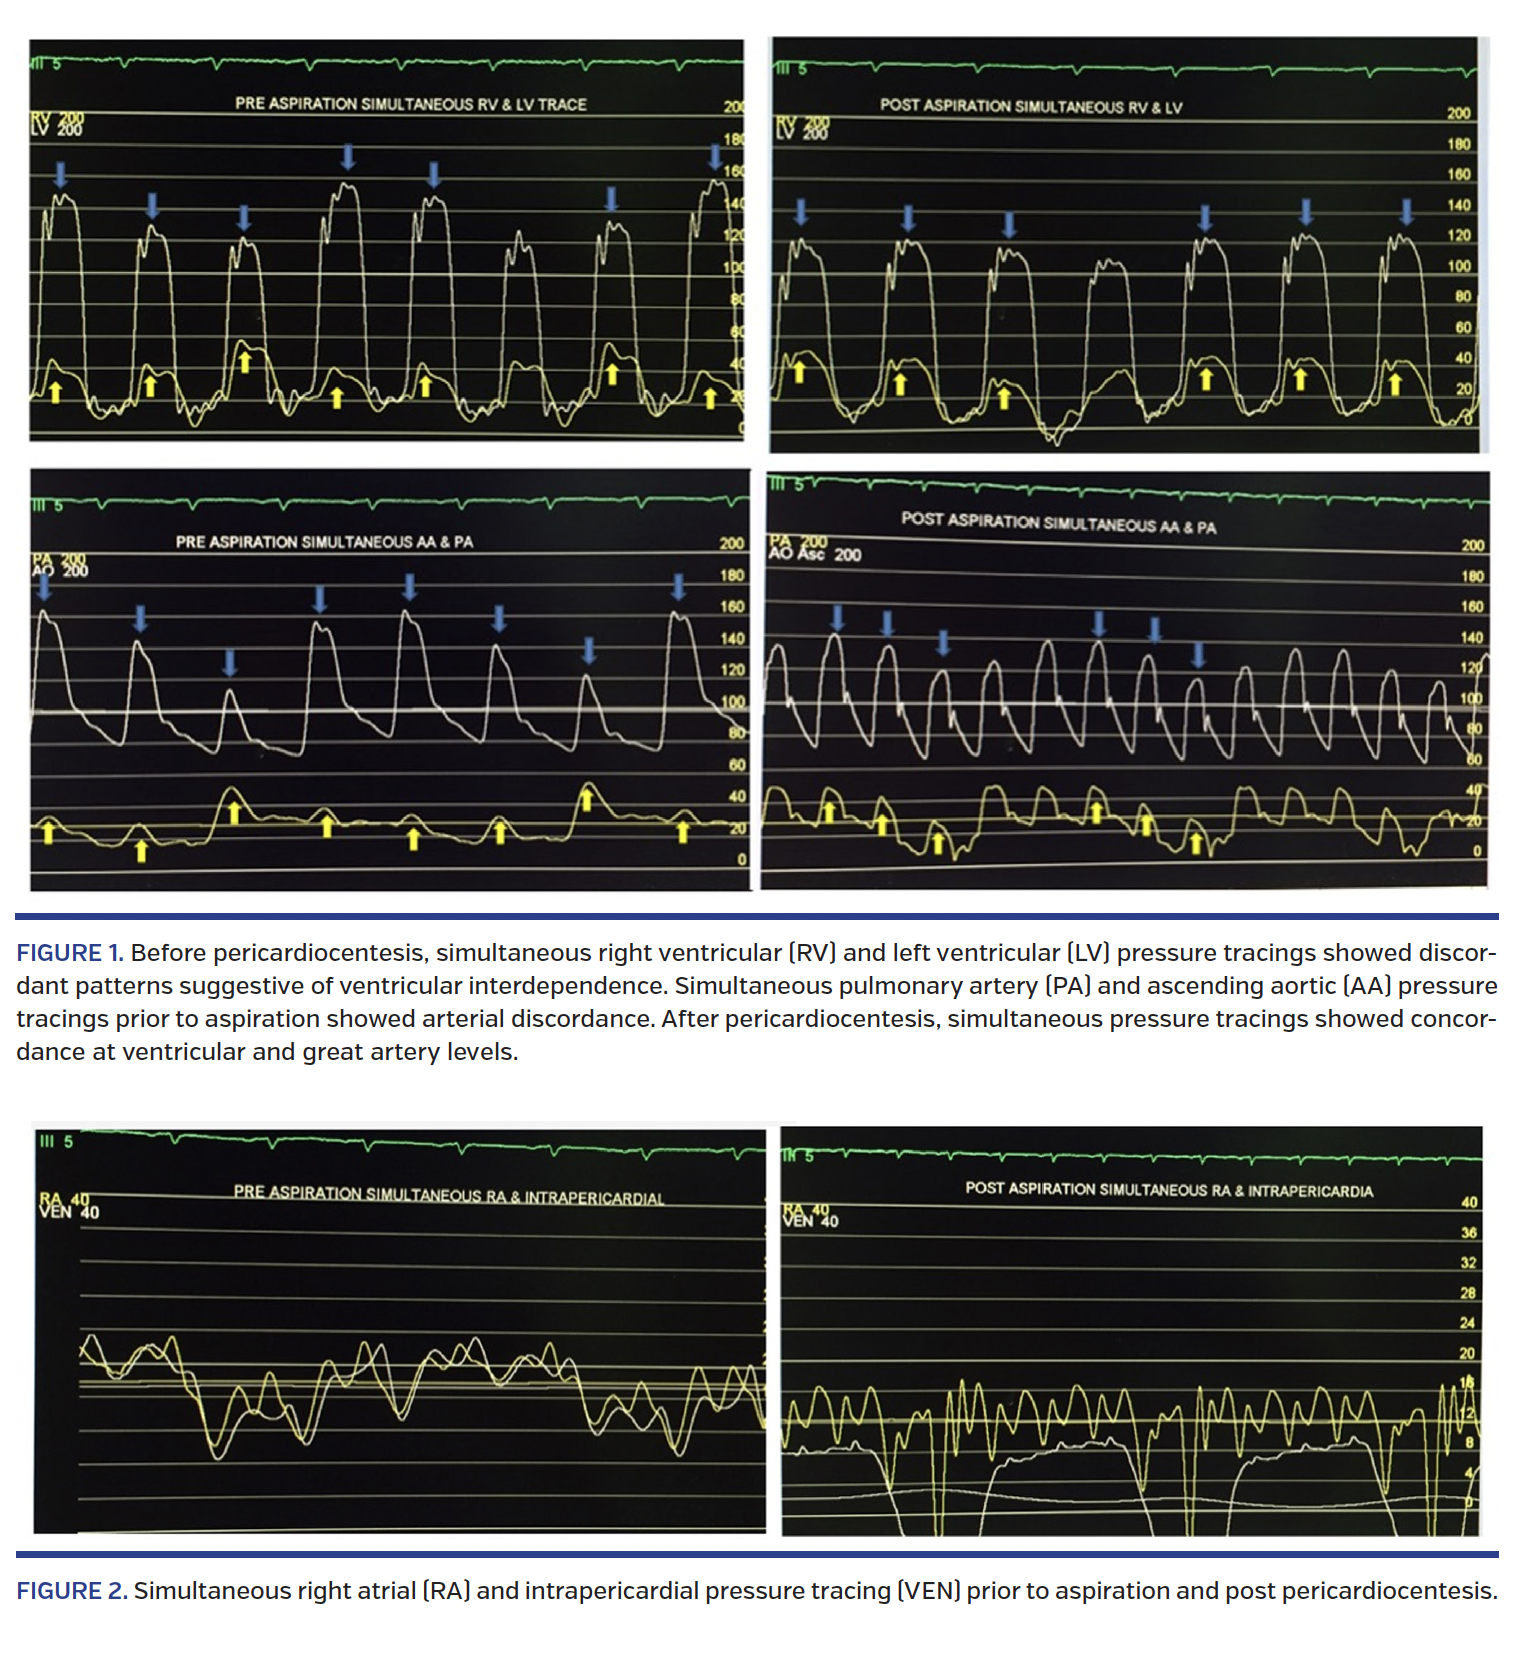

The hemodynamic studies at baseline and post pericardiocentesis demonstrated interesting findings, ie, equalization of the ventricular diastolic and intrapericardial pressures consistent with tamponade physiology. Simultaneous pressure tracing showed ventricular interdependence with discordant relationship of the left and right ventricles. Interestingly, a simultaneous main pulmonary artery and ascending aortic pressure recording showed similar discordant relationship of pressures in the great arteries (Figure 1). While the systolic pulmonary artery pressure increased at inspiration, this was accompanied by a fall in systolic ascending aortic pressure. The converse was noted in expiration, suggesting arterial discordance.

Pericardiocentesis produced 450 mL of hemorrhagic fluid and restored the mean intrapericardial pressure to 0 mm Hg. Pericardiocentesis resulted in reappearance of the “y” descent (Figure 2). The right atrial mean pressure remained elevated, although the intrapericardial pressures were restored to 0 mm Hg. Neither diastolic pressure equalization nor ventricular or arterial discordance could be demonstrated post pericardiocentesis.